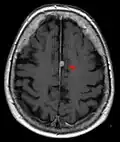

False color MRI by applying red to T1, green to PD and blue to T2.